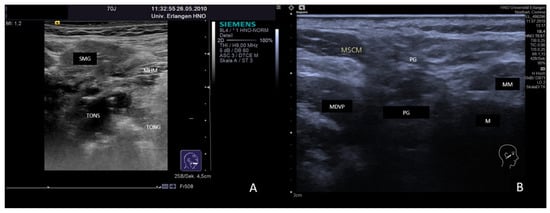

3.4.2. Chronic Recurrent Juvenile Parotitis

3.4.3. Sjoegren’s Syndrome/Disease